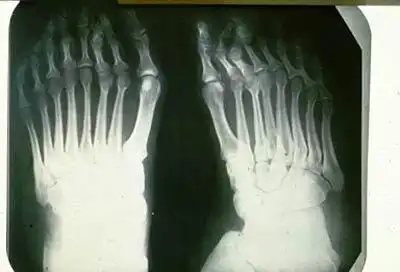

Шестипалость... Собственно, эта паталогия в этих местах и за болезнь-то не считается, - так, баловство, жить не мешает...

Но кроме шестипалых, здесь были зарегистрированы и восьмипалые дети...